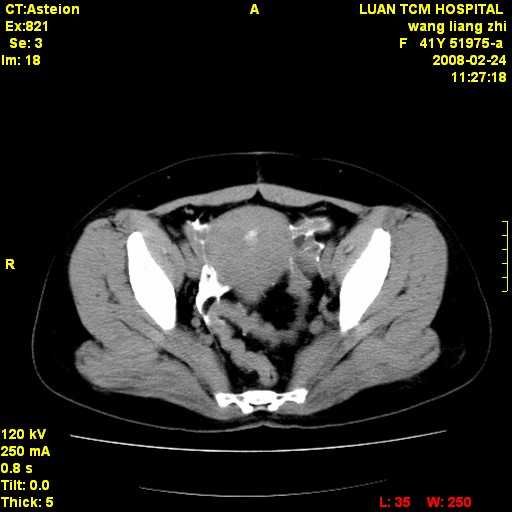

以下是引用dyqct在2009-8-23 16:17:00的发言:[br]考虑:1、造影剂进入腹腔、结肠旁沟、肝周;[br] 2、子宫明显增大(腺肌增生症?);[br] 3、膀胱显影是由于造影剂吸收后经肾分泌进入膀胱的;[br] 4、建议mri检查子宫。

以下是引用zjzjr在2009-8-23 17:28:00的发言:[br]考虑:1、造影剂进入腹腔、结肠旁沟、肝周;[br] 2、子宫明显增大(腺肌增生症?);[br] 3、膀胱显影是由于造影剂吸收后经肾分泌进入膀胱的;[br] 4、建议mri检查子宫。